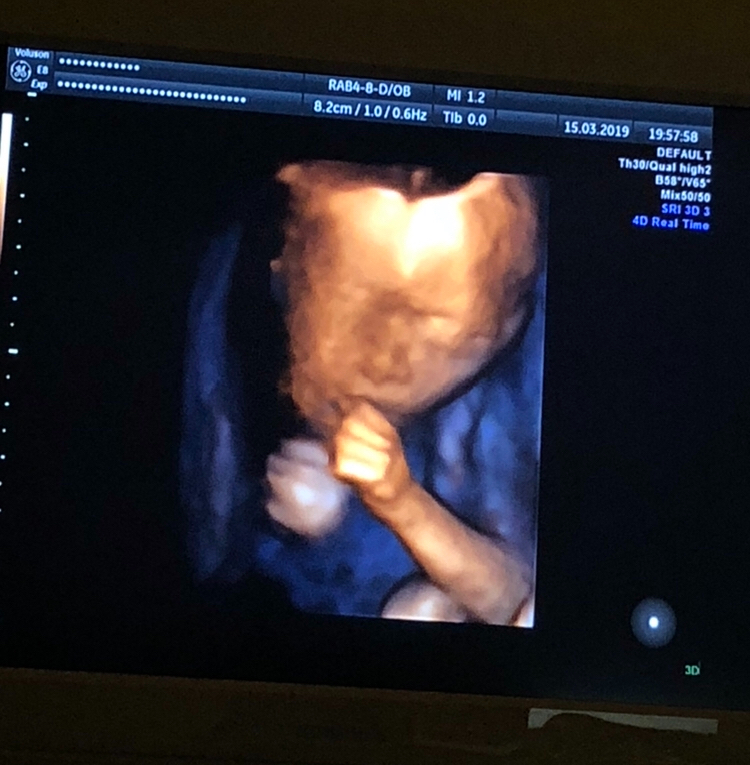

20 недель,2-ой скрининг,фото 3D

Результаты: УЗИ, КТГ, доплера, скринингаВчера было ровно 20 недель,2 скрининг,посмотрела как он вырос,такой хорошенький,палец сосал)) весит 350 гр. Все у него хорошо ттт. Хоть тут многие и говорили,что в 13 недель это рано для определения пола,но я считаю что нет,все зависит от врача,вчера специально даже спросила ее ошибалась ли она на сроке 13 недель с полом(первого,второго и этого третьего езжу только к ней скрининги делать), сказала,что с 13 недель она ни разу не ошибалась,что с такого срока уже все понятно. Вчера только подтвердила,что это ещё один мальчик😂. В спб она одна из лучших узи специалистов и кто скрининги делает идеально. Вдруг кому понадобится фамилия ее Лисина,работает в роддоме на фурштатской. Малыш вчера идеально лежал,шевелился во всю,показывая себя во всей красе и во всех ракурсах,видимо хотел угодить отцу,который тоже приехал посмотреть)) И фото мне на память,на ББ всегда проще зайти и посмотреть фото,чем потом искать их дома)) 😄😄